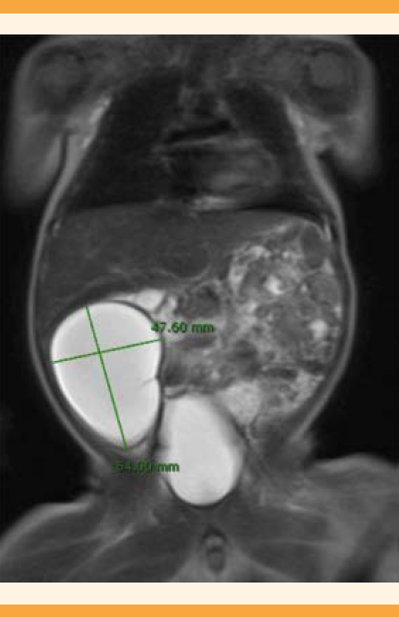

Nació un varón de 3720 gramos mediante parto eutócico. El posparto trascurrió sin contratiempos y el recién nacido se encontró asintomático, aunque en la exploración física se palpó una masa en la parte media derecha del abdomen, de apariencia móvil y no dolorosa. La ecografía abdominal de los primeros días de vida mostró, en el flanco derecho, una lesión de 52 x 34 x 59 mm sugerente de quiste de duplicación del intestino delgado, con el signo de la doble pared y contenido quístico, con ecogenicidades puntiformes en su interior. No se la encontró asociada con complicaciones de obstrucción intestinal o líquido libre intraabdominal. La resonancia magnética nuclear (Figura 2) y el estudio del tránsito intestinal con contraste hipoosmolar (diatrizoato) apoyaron el diagnóstico de sospecha referido y la ausencia de comunicación de la lesión con la luz intestinal. No fue posible descartar otras lesiones quísticas intraabdominales, como los quistes de epiplón o mesentéricos. En la laparoscopia exploradora practicada a las dos semanas de vida extrauterina se objetivó un quiste de duplicación intestinal, incluido en el borde mesentérico intestinal, de aproximadamente, 6 x 5 a 6 cm de la válvula ileocecal. Se procedió a su resección junto con la porción intestinal contigua y a su anastomosis término-terminal. El estudio anatomopatológico confirmó el diagnóstico de duplicación intestinal ileal, sin comunicación con la luz intestinal. El curso posoperatorio inmediato y al mes fue favorable, con el recién nacido asintomático y en seguimiento por parte de los especialistas del servicio de Cirugía Pediátrica.

Figura 2 Resonancia magnética nuclear toracoabdominal del recién nacido. En el flanco derecho se observa una tumoración quística de 62 x 44 x 48 mm debidamente delimitada, compatible con quiste de duplicación intestinal, de pared lisa con un septo fino incompleto y contenido líquido homogéneo. No demuestra dependencia del hígado, vías biliares ni riñón derecho. No se observan signos de obstrucción intestinal, líquido libre ni otras alteraciones.